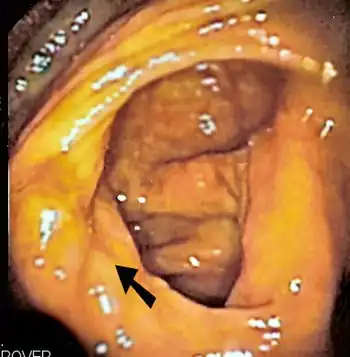

The ileocecal valve prevents reflux of bacteria from the colon into the small bowel. Resection of the valve can lead to bacterial overgrowth. | |

Finally, abnormal connections between the bacteria-rich colon and the small bowel can increase the bacterial load in the small bowel. Patients with Crohn's disease or other diseases of the ileum may require surgery that removes the ileocecal valve connecting the small and large bowel; this leads to an increased reflux of bacteria into the small bowel. After bariatric surgery for obesity, connections between the stomach and the ileum can be formed, which may increase bacterial load in the small bowel.[21]